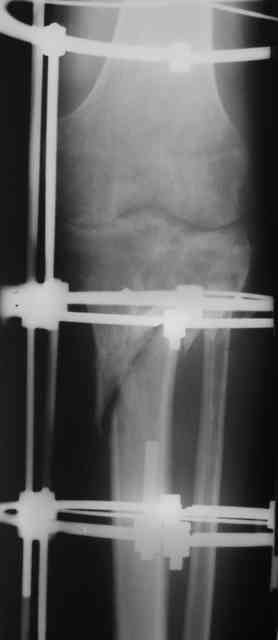

Р-граммы и фото за 4.05.2007 - 7-е сутки после операции.

Ход операции - линейным разрезом по передней поверхности голени обнажена зона ложного сустава большеберцовой кости. От кости отсепарованы медиально м/ткани. Из зоны ложного сустава убраны рубцовые ткани, мобилизован дистальный отломок. По передней поверхности удалены два осколка, связанных грануляциями. Произведено удаление грануляционной ткани из проксимального отломка (на вид сине-серого цвета), "чистого" гноя не было. Затем произведено наложение аппарата и репозиция отломков. По передне-медиальной поверхности образовался дефект до 4х2х2 см + полость в проксимальном отломке. Удаленные осколки очищены от грануляций, уложены в место дефекта, зажаты между отломками. После иссечения раны по передней поверхности, находящейся рядом с операционной раной, последняя ушита с большим натяжением.

Перелом мыщелка сросся. Проксимальный отломок очень порозный.

На перевязках - из раны небольшое кол-во сукровичного отделяемого. Отек голени умеренный, состояние кожи на фото.

Аппарат видел, репозиции не заметил. О "наложенном" аппарате: спицы в проксимальном отломке б\берцовой кости проведены очень низко, и опять только две, как и в первом аппарате. Почему только одна спица в дистальном парафрактурном кольце? Проксимальная база на бедре должна улучшить стабильность проксимального фрагмента tibia? Ничего подобного двумя спицами в одной базе при таком длинном рычаге вы не добьетесь, а вот совсем потерять движения в коленном суставе они почти гарантируют.

О репозиции: мыщелок сросся и слава Богу, но основные отломки фиксированы в вальгусном положении, собственно как и было, это критично. В чем состояла репозиция?

Согласен с оценкой Алексея. Секцию на бедро не нужно, на ровном месте сформируется контрактура коленного сустава. В проксимальный эпиметафиза большеберцовой ввели бы 4-5 спиц с упорами, в том числе в виде петли, и хватило бы.

Конечно, остеотомия для удлиннения должна быть в этом случае дисьальная. А будущее вероятно не такое уж и отдаленное.

Только на шарнирах. Но спиц в проксимальный отломок добавить, а базу с бедра снять.